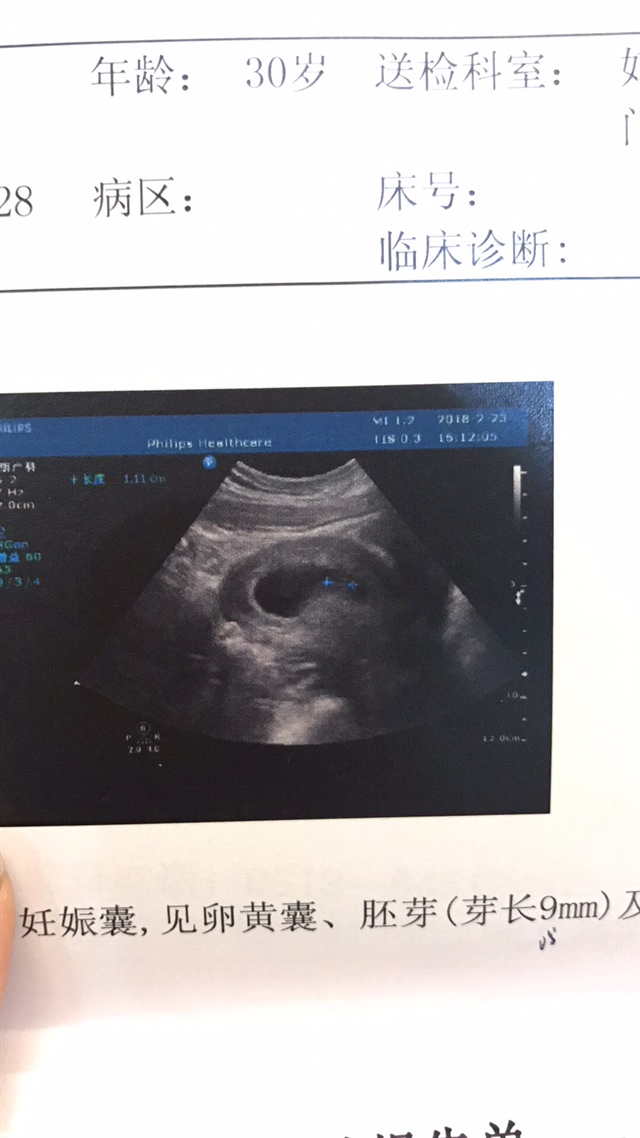

孕5周+4天

接宫内好运,好希望我的宝宝也这么好。